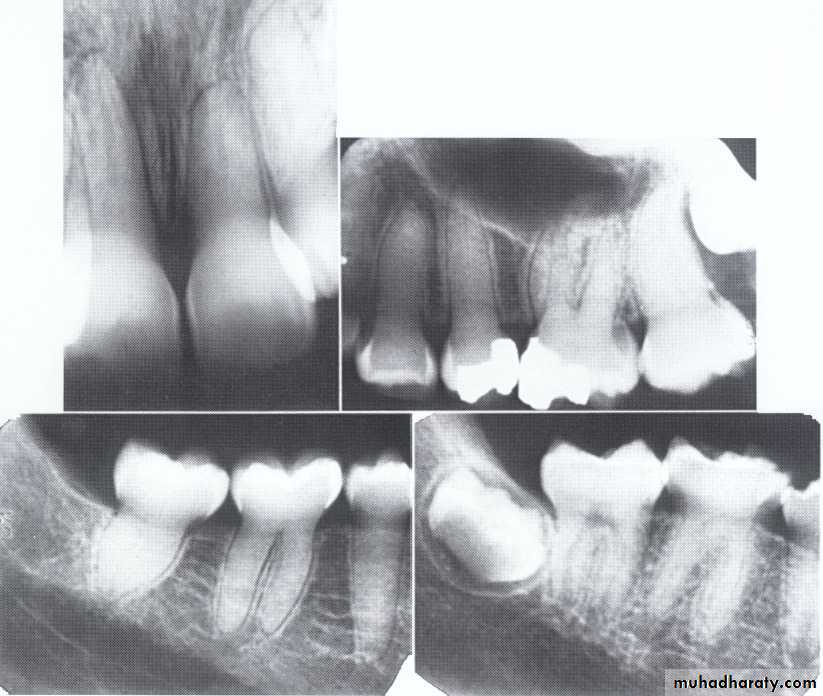

Type II (Coronal Type)

Dentin dysplasia, type II. panoramic &periapical films of the same case show obliteration of the pulp chamber, reduction in the caliber of root canals, and pulp stones obscuring the flame-shaped pulp chambers.

Periapical inflammatory lesions are associated with some of the mandibular anterior teeth.

Regional Odontodysplasia(ghost teeth)

Usually localized to a certain area and nonhereditary.

The enamel, dentin, and pulp of teeth are affected, and on radiographs the teeth are described as "ghost teeth".Unknown etiology.

It most commonly affects the maxillary anterior teeth of both the permanent and primary dentitions.

Teeth affected may exhibit a delay or total failure in eruption.

Treatment:Most dentists will advocate extracting the affected teeth as soon as possible and inserting a prosthetic replacement.